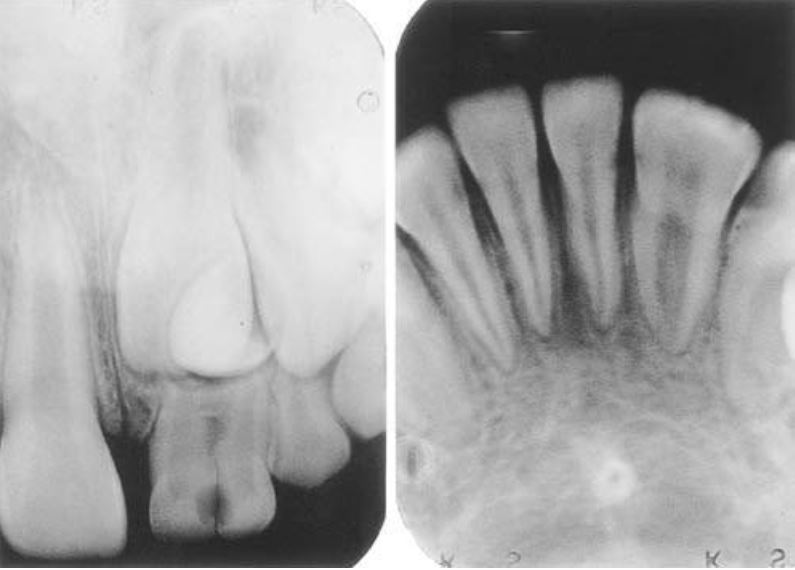

Răng dung hợp (fusion)

Xảy ra khi 2 mầm răng riêng rẽ nhập lại với nhau. Phần răng dung hợp thường chỉ chứa ngà và đôi khi chứa cả men.

Tỉ lệ gặp trên răng sữa cao hơn gấp 5 lần so với răng vĩnh viễn và thường xuất hiện cả hai bên hơn là một bên.

Răng thường bị ảnh hưởng nhiều nhất là các răng cửa. Răng dung hợp thường có một rãnh khá sâu chạy dọc theo mặt ngoài hoặc mặt trong và một khía ở rìa cắn tại vị trí mà 2 răng hợp lại. Trên phim X quang, răng dung hợp có 2 buồng tủy riêng biệt.

Răng sinh đôi cũng hay có rãnh dọc theo mặt ngoài hoặc mặt trong, khía ở rìa cắn. Trên lâm sàng rất khó chẩn đoán phân biệt giữa răng dung hợp với răng sinh đôi.

Trên phim thì thấy răng sinh đôi chỉ có một buồng tủy rất rộng, chân răng to, thân răng chẻ đôi. Tuy vậy vẫn còn nhiều biến thể khác.